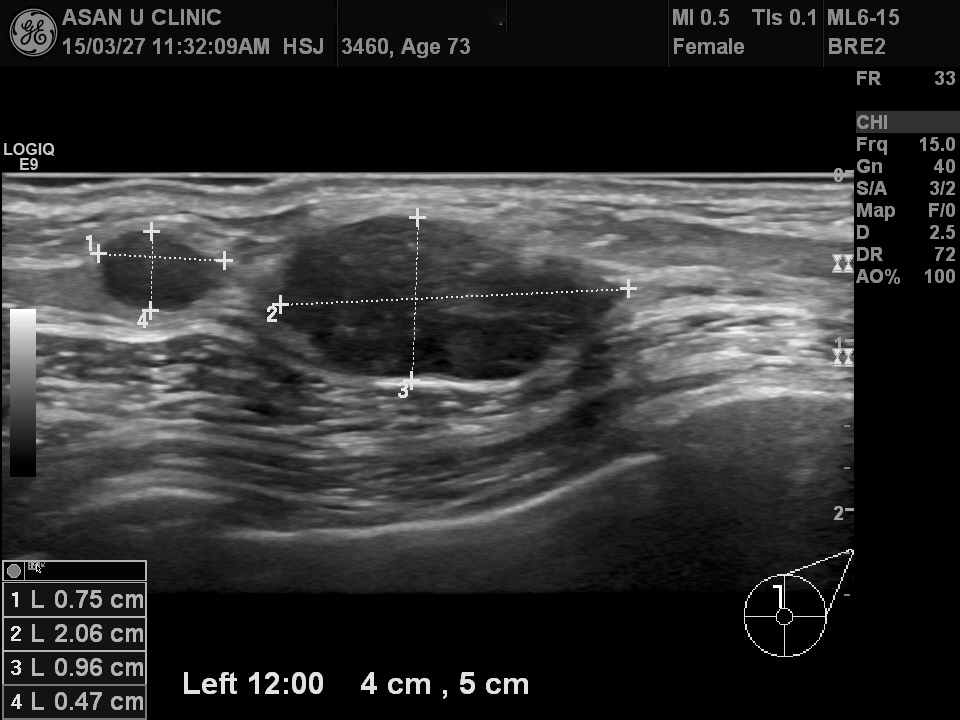

73세 여성분입니다.

건강검진상 이상소견으로 내원하셨지만, 혹이 만져지기도 합니다.

조직검사상  침윤성 유관암으로 진단되셨습니다.